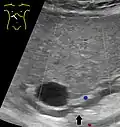

Choledocholithiasis (stones in common bile duct) is one of the complications of cholelithiasis (gallstones), so the initial step is to confirm the diagnosis of cholelithiasis. Patients with cholelithiasis typically present with pain in the right-upper quadrant of the abdomen with the associated symptoms of nausea and vomiting, especially after a fatty meal. The physician can confirm the diagnosis of cholelithiasis with an abdominal ultrasound that shows the ultrasonic shadows of the stones in the gallbladder.

The diagnosis of choledocholithiasis is suggested when the liver function blood test shows an elevation in bilirubin and serum transaminases. Other indicators include raised indicators of ampulla of vater (pancreatic duct obstruction) such as lipases and amylases. In prolonged cases the international normalized ratio (INR) may change due to a decrease in vitamin K absorption. (It is the decreased bile flow which reduces fat breakdown and therefore absorption of fat soluble vitamins). The diagnosis is confirmed with either a magnetic resonance cholangiopancreatography (MRCP), an endoscopic retrograde cholangiopancreatography (ERCP), or an intraoperative cholangiogram. If the patient must have the gallbladder removed for gallstones, the surgeon may choose to proceed with the surgery, and obtain a cholangiogram during the surgery. If the cholangiogram shows a stone in the bile duct, the surgeon may attempt to treat the problem by flushing the stone into the intestine or retrieve the stone back through the cystic duct.